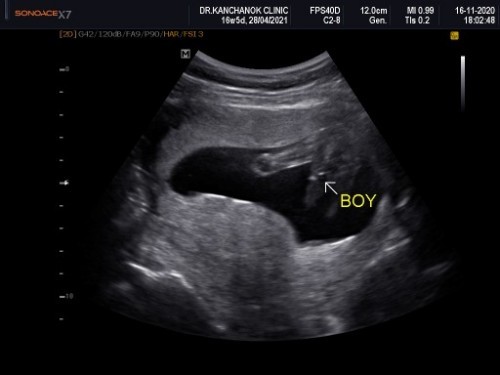

ผช.ครับ

ผช.ค่ะ